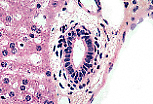

闰管 - 赫林管(Hering管)

胆小管将肝细胞分泌的胆汁输送至门管区(与血液流动方向相反)。

接近门管区时,胆小管开口于短的、有独立管壁的管道; 该管道先由扁平细胞构成,后变为立方细胞,称为闰管(cholangioles)。 当闰管进入门管区时,有时称为赫林管(Hering管)。

赫林管位于门管区周边,可通过狭窄的管腔和单层立方上皮识别。

胆管

赫林管汇合成管径更大的胆管,胆管衬覆单层柱状上皮, 上皮外有少量同心圆排列的结缔组织支持。

管径较大的胆管中,柱状上皮细胞的顶端会形成纹状缘。